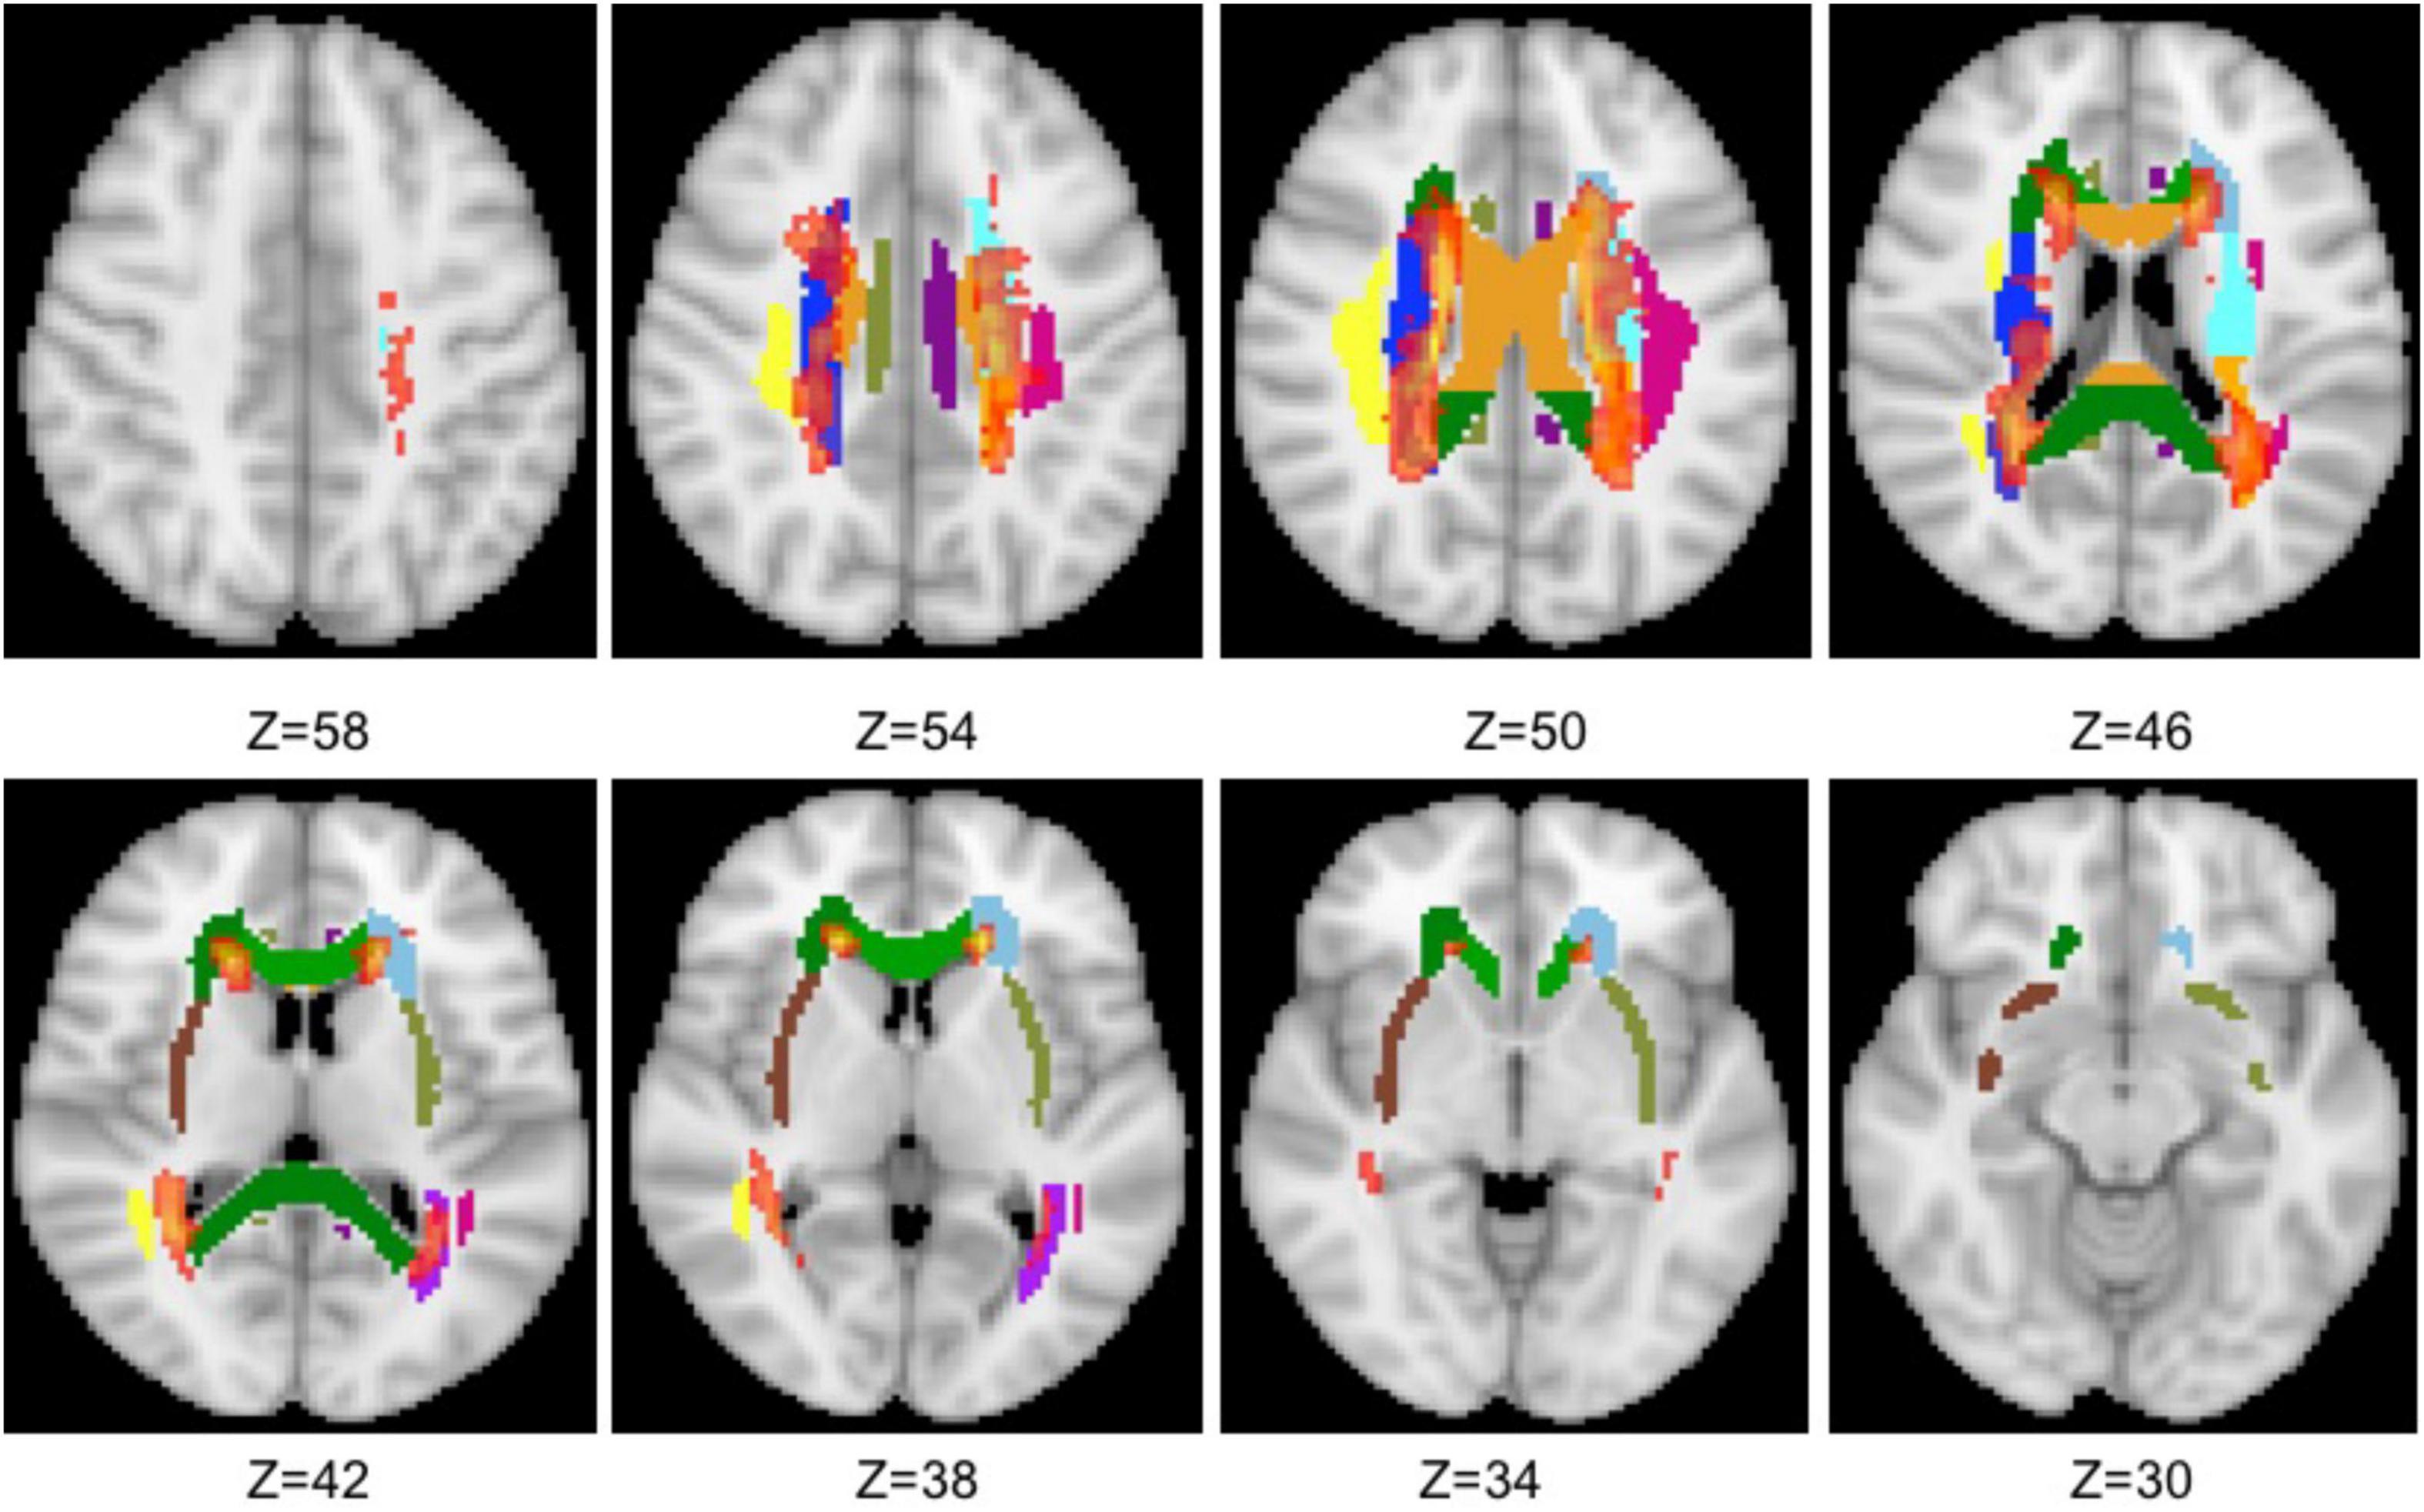

Amazon.com: Diffusion Tensor Imaging: A Practical Handbook,

Amazon.com: Diffusion Tensor Imaging: A Practical Handbook, Free-water diffusion tensor imaging detects occult,

Free-water diffusion tensor imaging detects occult, DTI Scalars (FA, MD, AD, RD) - How do they relate to brain,

DTI Scalars (FA, MD, AD, RD) - How do they relate to brain, Frontiers | Diffusion Tensor Imaging Revealed,

Frontiers | Diffusion Tensor Imaging Revealed, Diffusion Tensor MR Imaging and Fiber Tractography,Diffusion Tensor Imaging: A Practical Handbook 拡散テンソルイメージング 実用ハンドブック 拡散テンソル画像 英語 洋書古本です。レア.スタンサル Lea.Stansalフランスの手芸作家の本。英語です。ウェブスター英語大百科事典 1989年版 26万語掲載最高峰英語辞典。 表紙に経年によるスリ傷みあります。ハリーポッター ステッカーブック。 経年による小ヤケがありますが、 使用感がありますが、読むぶんには問題ないと思います。ラテン 英語のワークブック。他にも、類似、関連商品を多数出品しておりますので、ぜひご覧ください。64冊!!セールOxford Reading Tree stage6-9。

Diffusion Tensor MR Imaging and Fiber Tractography,Diffusion Tensor Imaging: A Practical Handbook 拡散テンソルイメージング 実用ハンドブック 拡散テンソル画像 英語 洋書古本です。レア.スタンサル Lea.Stansalフランスの手芸作家の本。英語です。ウェブスター英語大百科事典 1989年版 26万語掲載最高峰英語辞典。 表紙に経年によるスリ傷みあります。ハリーポッター ステッカーブック。 経年による小ヤケがありますが、 使用感がありますが、読むぶんには問題ないと思います。ラテン 英語のワークブック。他にも、類似、関連商品を多数出品しておりますので、ぜひご覧ください。64冊!!セールOxford Reading Tree stage6-9。